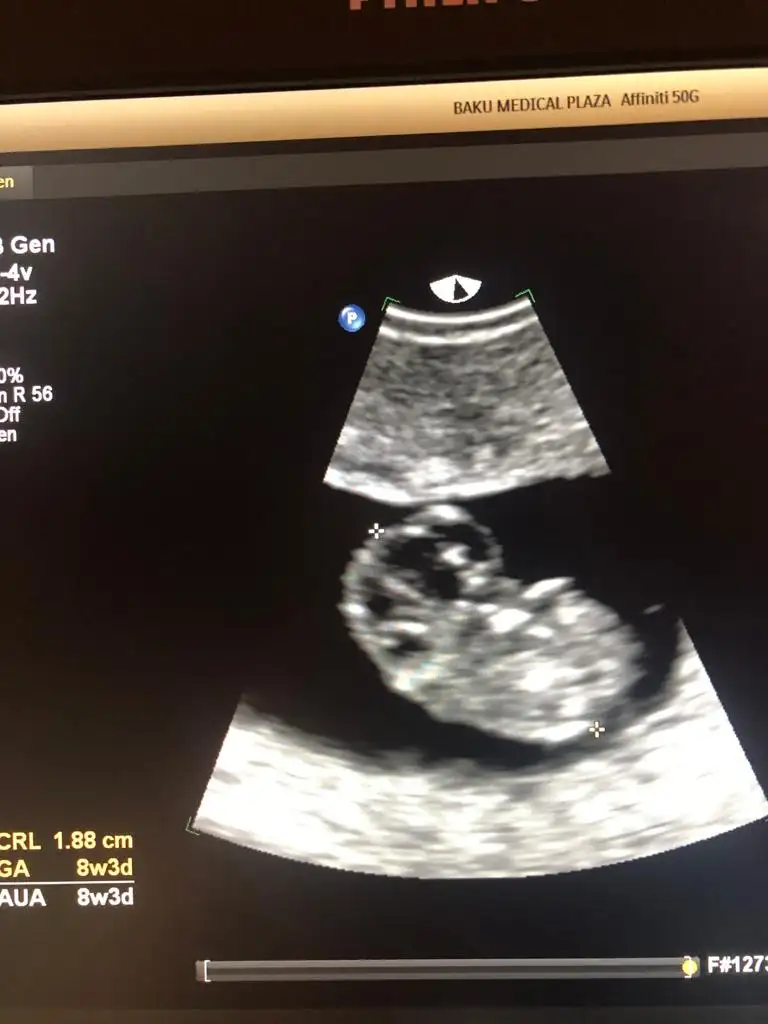

dr soylemeden siz gorun genital nub teorisi ( bebegin cinsiyeti)

Merhabalar bende yarın doktora gideceğim bakalım varmi bir yorumunuz bana da :)

Eklentiler

• image.webp

image.webp

18,6 KB · Görüntüleme: 52